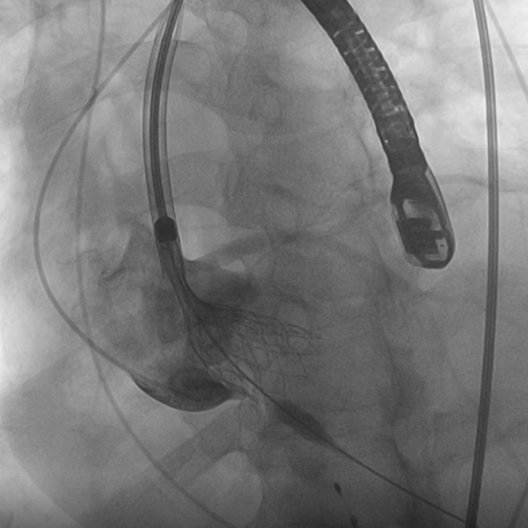

对于此例病人,严重横位心75°,器械需要出色的柔顺性与通过性在手术过程不损伤血管;瓣膜需要良好的径向支撑力,避免出现下滑的风险。在武汉大学中南医院心脏中心结构性心脏病团队通力协作下,顺利完成此例高难度手术,术中评估TaurusElite AV29mm瓣膜锚定良好,术后造影结果显示瓣膜形态、位置良好,仅少量瓣周漏。手术即刻超声测量,主动脉瓣工作良好,瓣口流速从术前的5.2m/s改善为1.8m/s,跨瓣压差从术前的106mmHg改善为8mmHg。

23mm球囊预扩

TaurusElite顺利过弓与跨瓣

瓣膜释放脱钩

即时心脏彩超评估

术后造影评估